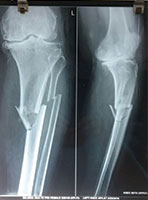

Case 4: Tibial Fracture

70 Years female fell in the bathroom and sustained injury to his left leg. She had fracture of left leg (tibia and fibula)

X-RAY 1

Pre operative x-ray showing fracture both bone left leg

X-RAY 2

Post operative Xray

X-RAY 3

Post op xray tibial fracture fixed with interlocking nail